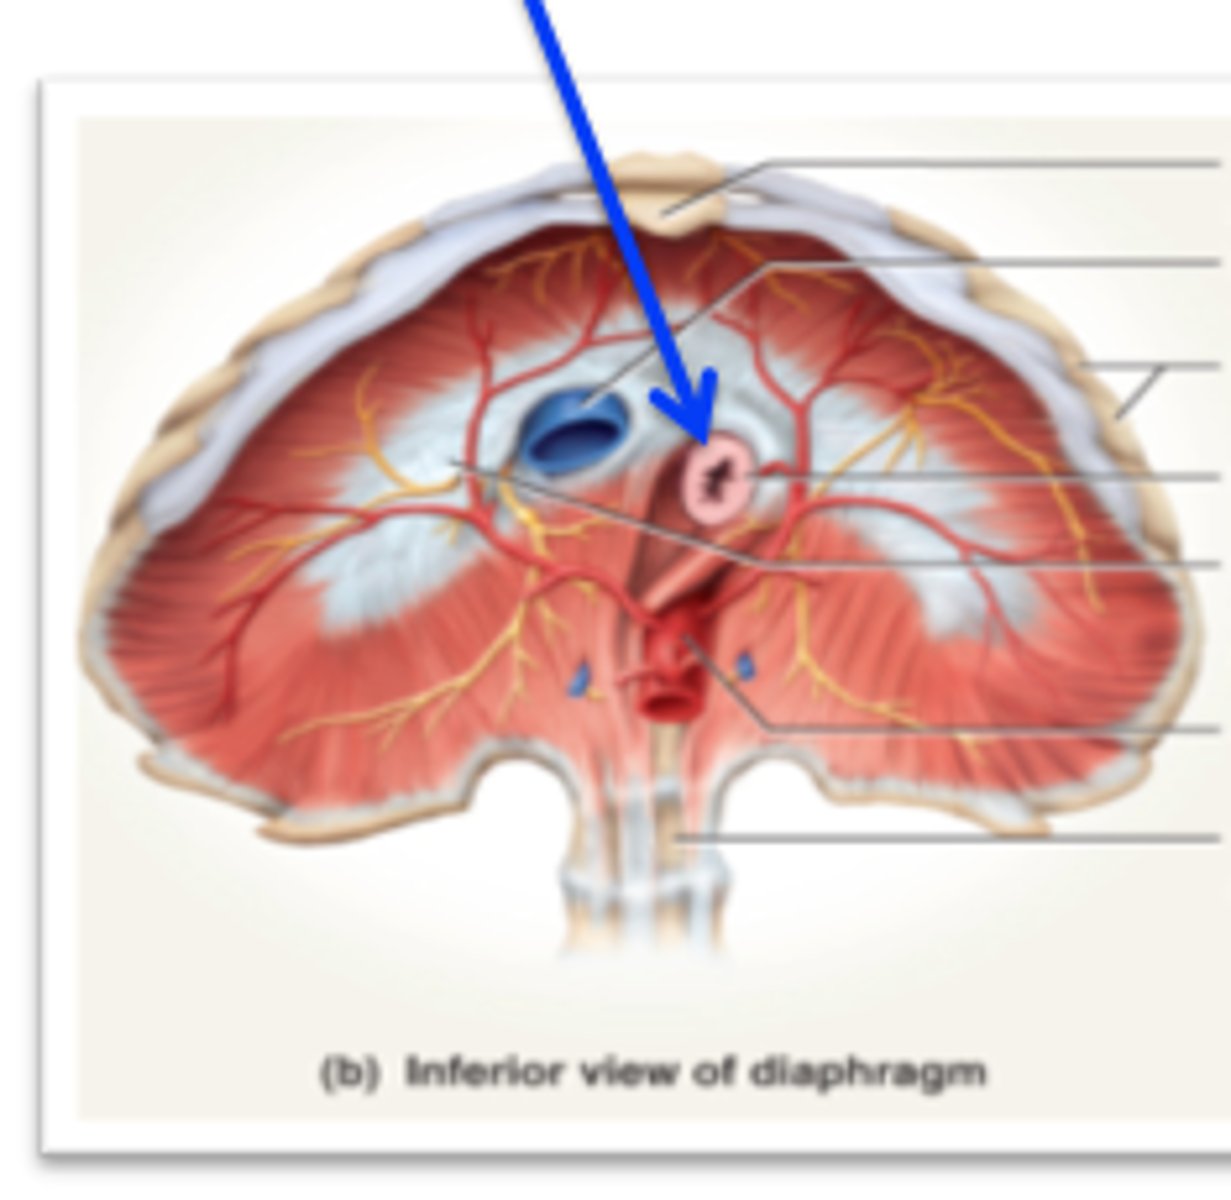

esophageal hiatus

hole in diaphragm for esophagus